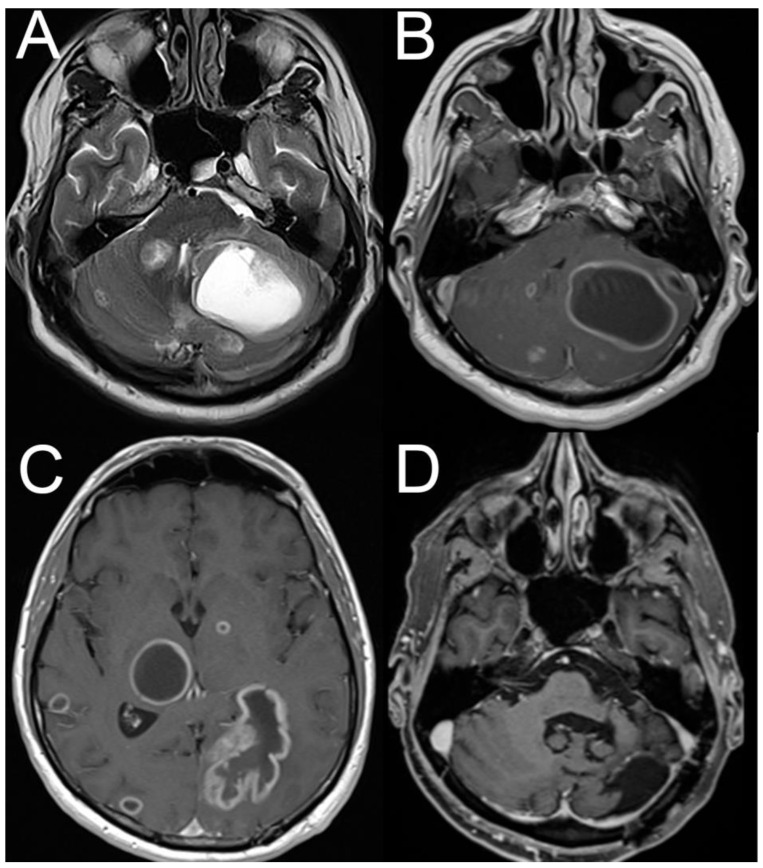

新发眩晕、头晕和步态不平衡是急诊科最常见的症状,占所有患者的2.1-4.4%。这些患者的潜在病因范围广泛,涉及许多专业,这往往导致诊断上的挑战。对于符合急性前庭综合征(AVS)诊断标准的患者,即表现为急性发作的持续性眩晕/头晕,伴有步态不平衡、运动不耐受、恶心/呕吐,伴或不伴眼球震颤),典型的鉴别诊断为椎基底动脉卒中和急性单侧前庭病变。然而,其他疾病也可能出现AVS。这些包括非神经系统原因,如药物副作用或中毒、电解质紊乱、心脏病、严重贫血、一氧化碳中毒、内分泌失调等。其他非卒中性神经系统疾病也可能出现AVS或发作性眩晕/头晕,包括脱髓鞘性中枢神经系统疾病、后窝肿块病变、急性硫胺素缺乏症和前庭偏头痛。此外,急性生理异常(如低血压、发烧、严重贫血)可能会暴露先前已得到良好补偿的前庭损伤。在此,我们回顾急症室急性起病头晕的诊断方法,并讨论除中风和急性单侧前庭病变外最重要的鉴别诊断。